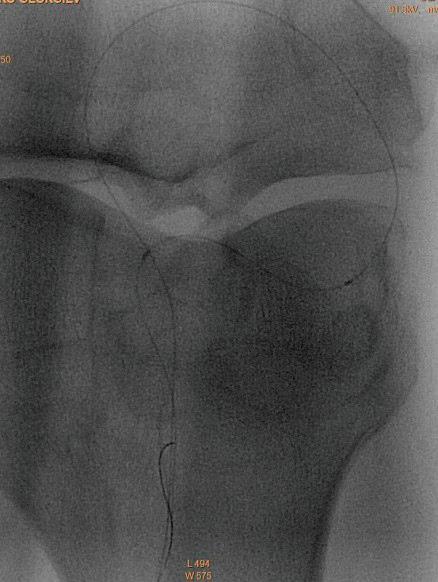

между m. constrictor pharyngis и горния полюс на тонзилата или между тонзиларната капсула и задната небна дъга (Фиг. 4). При него се изолира полимикробна флора. Преобладаващите организми са анаероби: Prevotella, Porphyromonas, Fusobacterium и Peptostreptococcus; аероби са: група А Streptococcus β-хемолитичен стрептокок, Стафилококус ауреус и Хемофи -

-

инфлуенца. Клинически се

на едната тонзила медиално, тризъм, „гъгнив” глас, повторно

ма се

за

изследване и се започва антибиотично лечение. В първите 2-3 дни, ако инцизията се е

и абсцес-тонзилектомия под

протекцията на масивни дози антибиотици. С оглед запазване на функцията на незасегнатата сливица при децата под 6 г. се съветва да се от-

страни само засегната сливица. След стихване на възпалителните изменения - 4 до 6 седмици е желателно да

бъде проведена тонзилектомия. Перитонзиларният абсцес може да доведе до застрашаващи живота на

детето усложнения: ретро- и парафа -

рингеален абсцес, медиастинит, тонзилогенен сепсис.